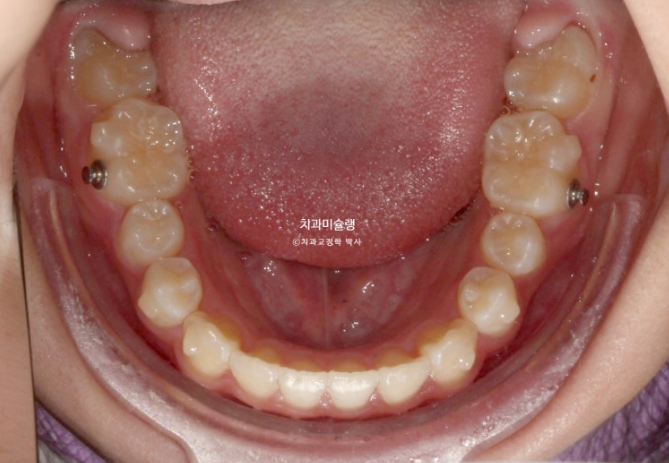

아직 빠지지 않은 상악 유치과 아직 덜 내려온 작은어금니를 좀 더 기다립니다.

완전한 영구치열에 접어들어 교합이 완성된 상태로 끝나면 유지장치도 그만큼 더 완벽하게 들어갑니다.

이후 약 7개월간 마지막 장치를 잘 때만 유지용으로 까면서 치료를 잠시 쉬어갑니다.

남은 유치가 빠지고 영구치가 나오기를 기다리는 시간입니다.

드디어 남은 유치가 다 빠졌습니다.

돌출 개선을 조금 더 도모하고자 두번째 세트 장치 제작에 들어갑니다.